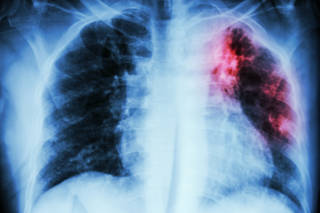

Une résistance malheureuse au traitement contre la tuberculose multirésistante

Une étude menée par lʹInstitut Tropical et de Santé Publique Suisse (Swiss TPH) montre que la résistance au nouveau régime de traitement de la tuberculose multirésistante récemment recommandé par lʹOMS se propage déjà entre les patients. Les résultats sont à lire dans le New England Journal of Medicine et soulignent l'importance d'améliorer les capacités de dépistage et de surveillance pour contrôler efficacement la propagation de la tuberculose multirésistante.

La tuberculose est très inégalement répartie dans le monde. C'est actuellement encore une maladie infectieuse très répandue dans le monde et une des causes majeures de décès.